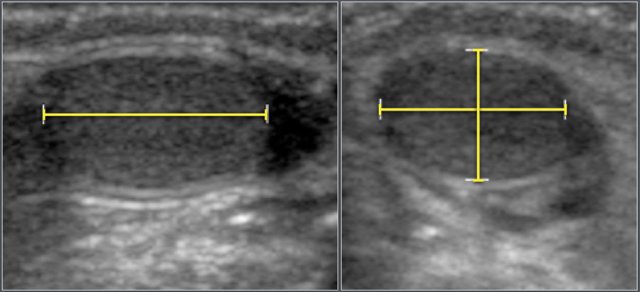

Kidney volume was calculated using the ellipsoid formula as Length x Width x Depth x 0.523.

Ultrasonographic measurement of the length, width an depth of a kidney.

Kidney volume is calculated using the ellipsoid formula as Length x Width x Depth x 0.523.